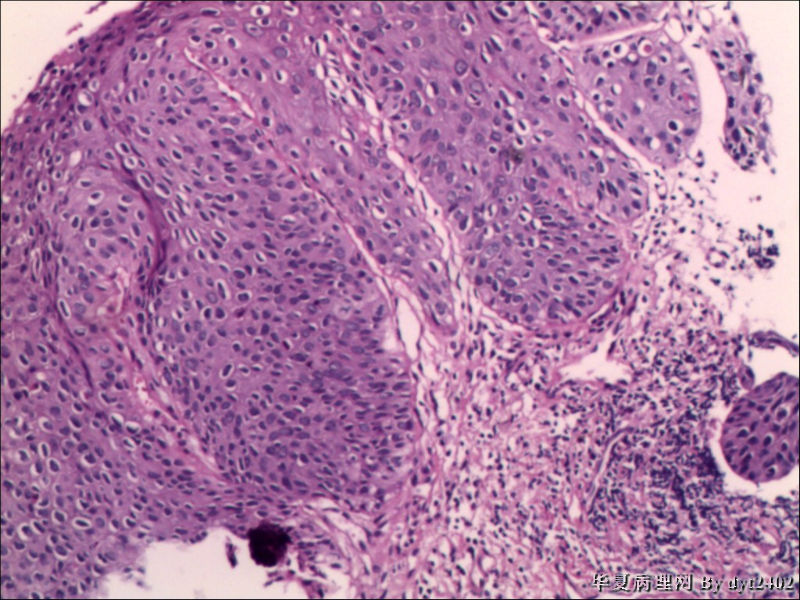

这样的外阴病变 发个原位癌是否合适?

• 这样的外阴病变 发个原位癌是否合适?图4

图4

原位癌够了,不排除其他地方有浸润。

似乎有浸润了

VIN III,做个银染或者标个免疫组化看一下基底膜是否完整。

看上去好像还完整 只是经常看见图5 那样结构的就觉得可能还有更重病变

VIN III